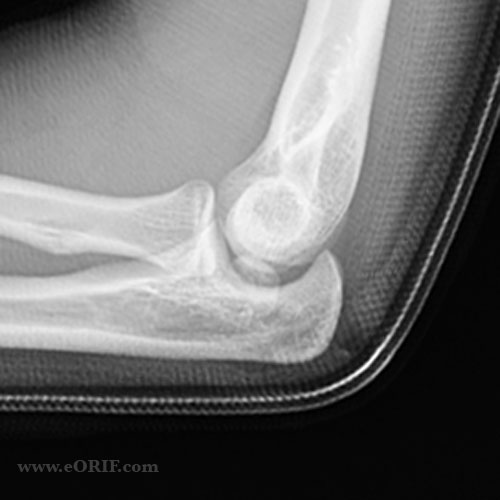

Greater Trochanter Hip Fracture S72.109A 820.20 eORIF from eorif.com

Diseases of the digestive system. The icd code s720 is used to code hip fracture a hip fracture is a serious femoral fracture that occurs in the proximal end of the femur (the long bone running through the thigh), near the hip. Search about 41 items found relating to hip fracture

821 fracture of other and unspecified parts of femur; The icd code s720 is used to code hip fracture a hip fracture is a serious femoral fracture that occurs in the proximal end of the femur (the long bone running through the thigh), near the hip.